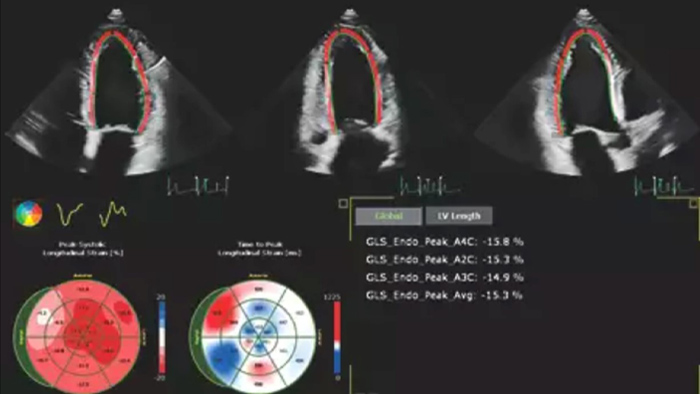

Robust and reproducible imaging tools are important to diagnose and monitor disease progression in heart failure. Current guidelines support the use of advanced echocardiography tools such as longitudinal strain and 3D assessment of LV and RV volumes and function.

Automation for robust, proven reproducible cardiac quantification in both 2D and 3D.

Quantification through Dynamic HeartModel.